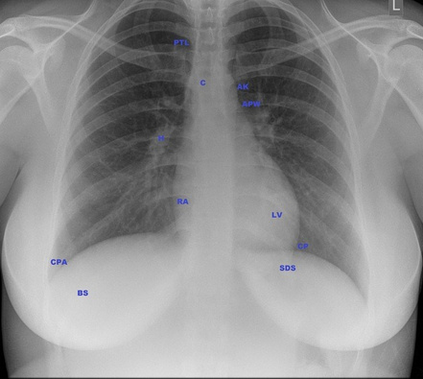

Artificial intelligence in healthcare requires models that are accurate and interpretable. We advance mechanistic interpretability in medical vision by applying Medical Sparse Autoencoders (MedSAEs) to the latent space of MedCLIP, a vision-language model trained on chest radiographs and reports. To quantify interpretability, we propose an evaluation framework that combines correlation metrics, entropy analyzes, and automated neuron naming via the MedGEMMA foundation model. Experiments on the CheXpert dataset show that MedSAE neurons achieve higher monosemanticity and interpretability than raw MedCLIP features. Our findings bridge high-performing medical AI and transparency, offering a scalable step toward clinically reliable representations.